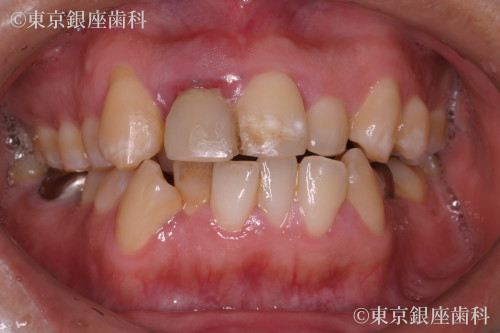

前歯の抜歯即時埋入イミディエートの症例

Before

疾患 前歯の欠損

施術内容 抜歯即時埋入イミディエート

治療期間 11カ月 費用 58万円(税込)

根破折により抜歯即時埋入、イミディエート